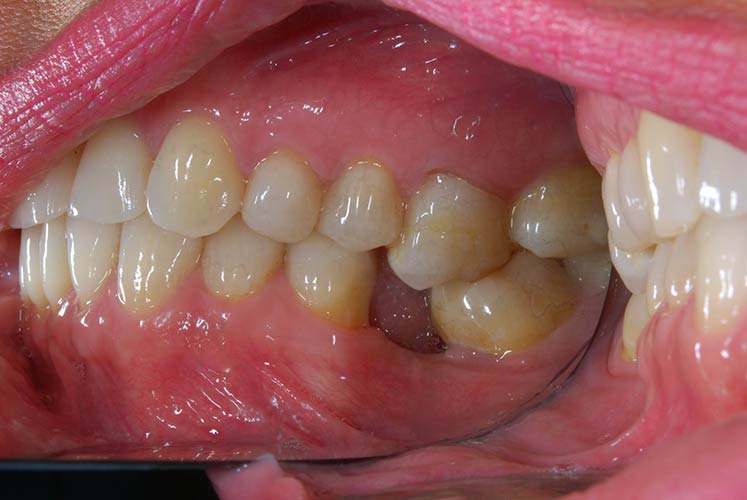

Con protesi fissa superiore e protesi fissa inferiore

I denti irrecuperabili dell'arcata superiore ed inferiore del paziente di anni 65

sono stati sostituiti da 10 impianti, cioè protesi radicolari endo-ossee che sostengono le protesi fisse superiore ed inferiore.